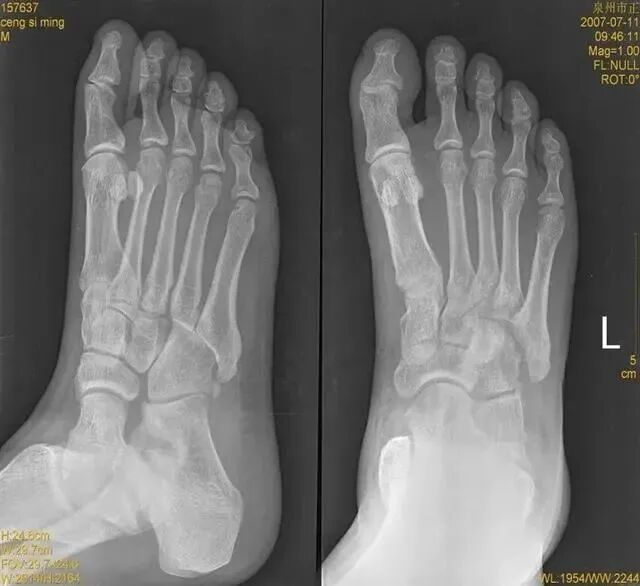

踝关节扭伤

是最常见的踝部损伤之一,据估计,全世界范围内每天每1万人中就有1人踝关节扭伤,扭伤可发生于运动员,也常见于普通人。

扭伤机制

旋后位扭伤最为常见;

距骨体前宽后窄,当踝关节背屈时,其宽部进入踝穴,能防止踝关节向后脱位;当跖屈时,其窄部进入踝穴,则关节不稳,易向侧方活动。